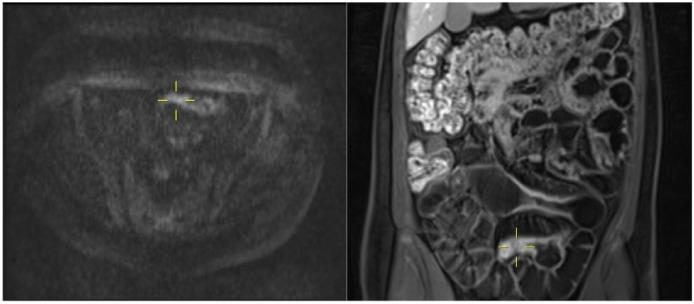

Treatment of Crohn's disease (CD) is intrinsically reliant on imaging techniques, due to the preponderance of small bowel disease and its transmural pattern of inflammation. Ultrasound (US), computed tomography (CT) and magnetic resonance imaging (MRI) are the most widely employed imaging methods and have excellent diagnostic accuracy in most instances. Some limitations persist, perhaps the most clinically relevant being the distinction between inflammatory and fibrotic strictures. In this regard, several methodologies have recently been tested in animal models and human patients, namely US strain elastography, shear wave elastography, contrast-enhanced US, magnetization transfer MRI and contrast dynamics in standard MRI. Technical advances in each of the imaging methods may expand their indications. The addition of oral contrast to abdominal US appears to substantially improve its diagnostic capabilities compared to standard US. Ionizing dose-reduction methods in CT can decrease concern about cumulative radiation exposure in CD patients and diffusion-weighted MRI may reduce the need for gadolinium contrast. Clinical indexes of disease activity and severity are also increasingly relying on imaging scores, such as the recently developed Lémann Index. In this review we summarize some of the recent advances in small bowel CD imaging and how they might affect clinical practice in the near future.